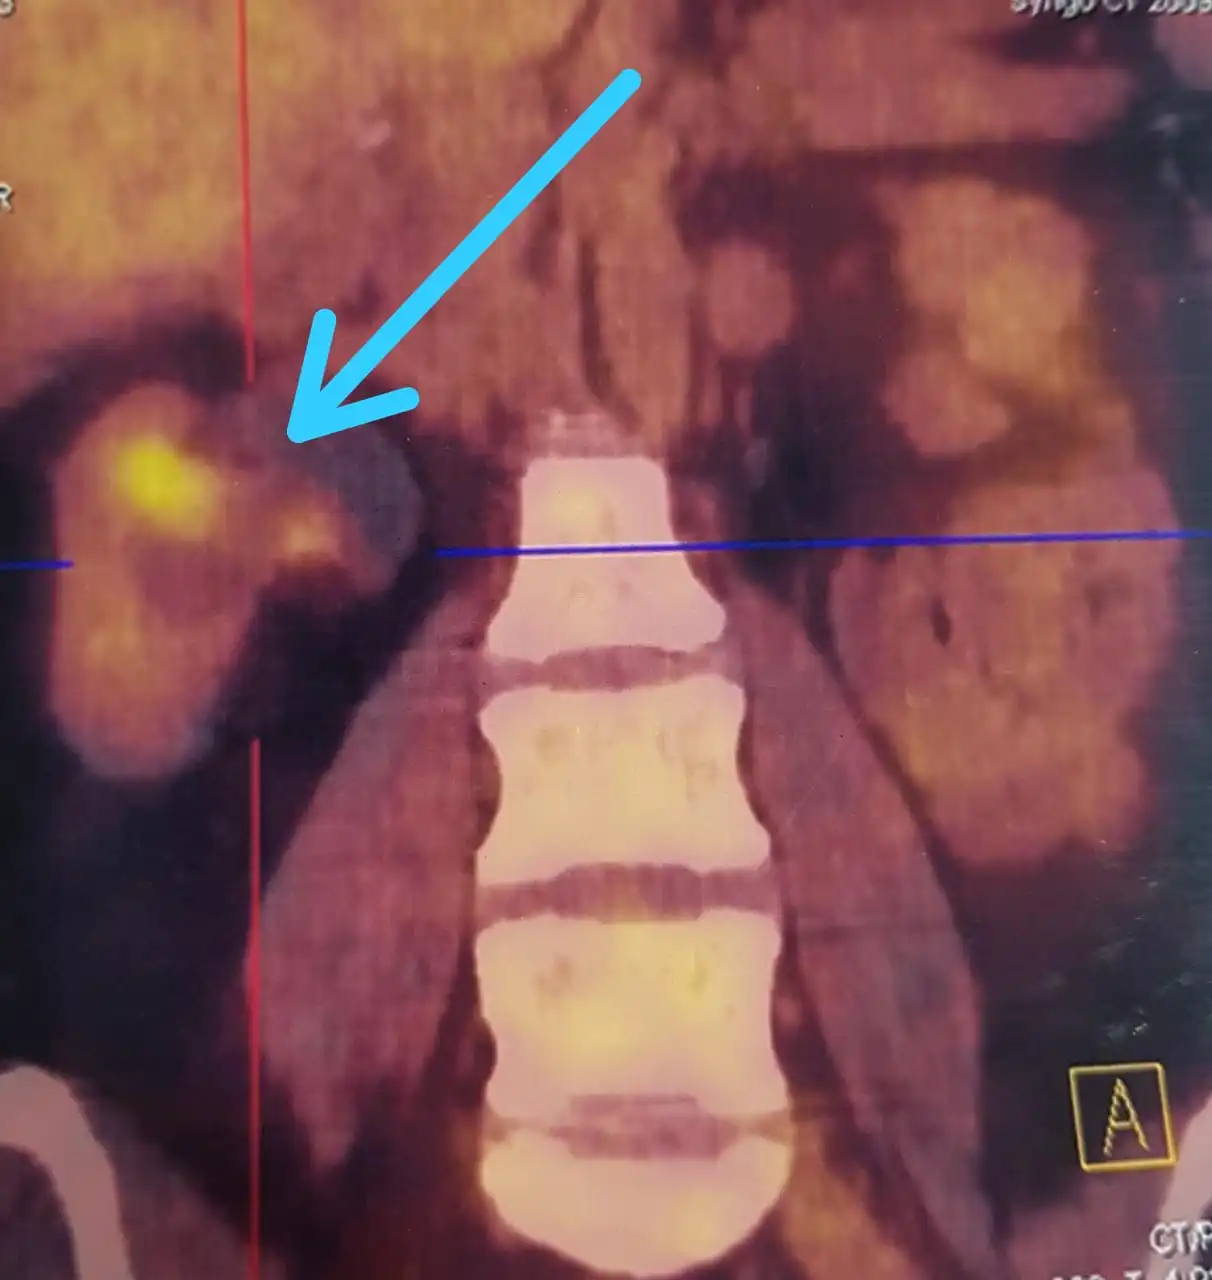

Bright area on PET scan suggesting cancer

Partial Nephrectomy for Hilar Renal Tumor in Young patient.

42 year old Omanian Female had an episode of blood in urine due to Kidney Cancer